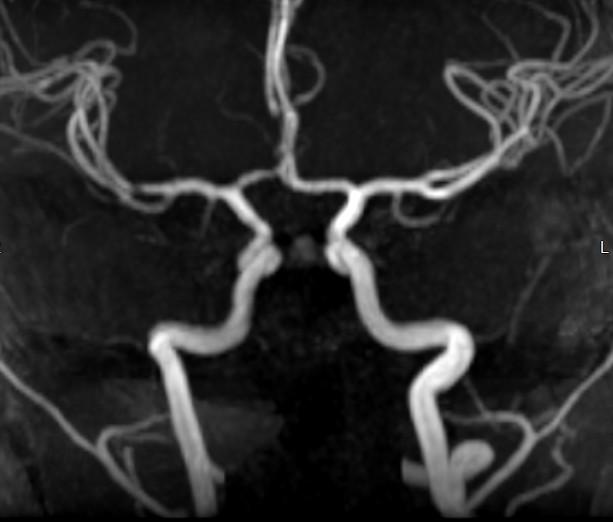

PEDS FAST Stroke MRI/MRA Brain 10 mins

Addition of Contrast, COW MRA, Black Blood T1 VASC

FAST "Black Blood" Imaging ACC T1 COR VASC 2 minutes

Focal Cerebral Arteriopathy of Childhood FCA-i

Mechanism unknown

Inflammation/Infection leading to Endothelial disruption, vasculopathy/vasculitis

In children, Moya Moya?

Black Blood Imaging (T1 VASC) vs Vessel Wall Imaging (VWI)

BB T1 COR VASC .8 mm resolution

Pick up collateral enhancement

• High Res VWI

• 3T (double the signal)

• .5 mm slice thickness

• Isotrophic

• When to image: 5-10 window after contrast administration

• 7-9 minutes sequence acquisition time